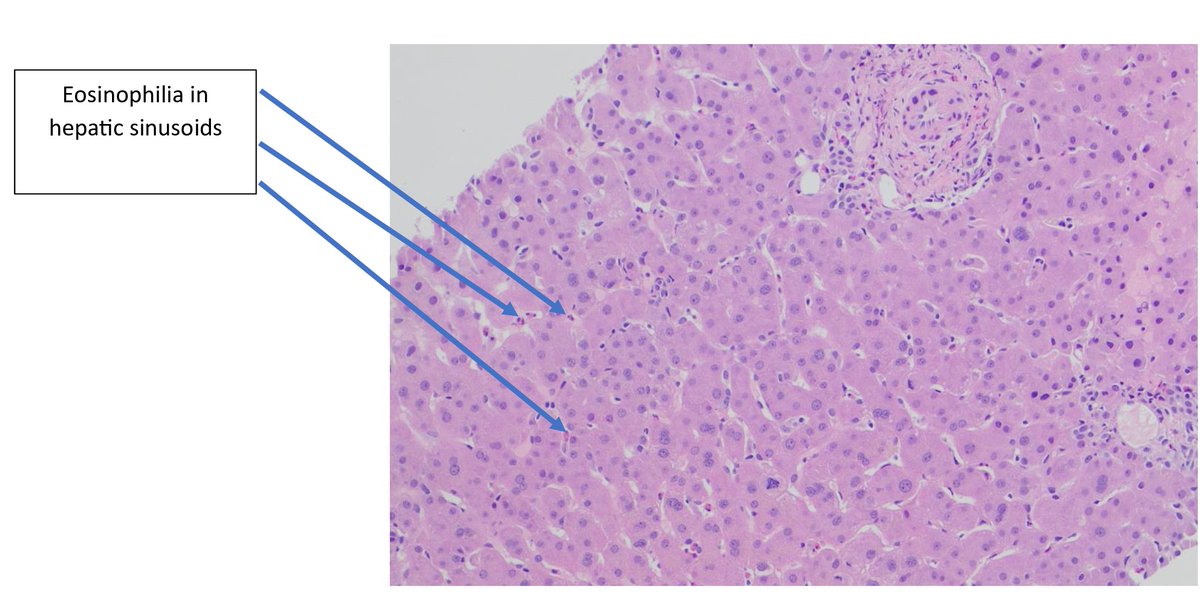

A 45-year-old male with EGPA history and positive p-ANCA showing rare liver involvement. Liver biopsy reveals eosinophilic infiltration. This case highlights how systemic vasculitis can impact any organ. #PathTwitter #Histopathology #EGPA #Vasculitis #EmoryHealthcare